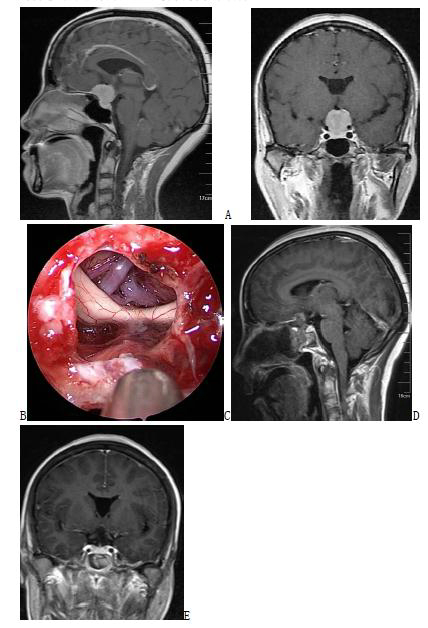

Neurosurgical Oncology Ward 3Neurosurgical Oncology Ward 3 (Middle-line skull base tumors and neuroendoscopy) Specialized features The Neurosurgical Oncology Ward 3 is characterized by the clinical application of neuroendoscopic technology. The annual number of neuroendoscopic surgeries exceeds 1200, and the quantity and quality of neuroendoscopic surgeries are leading domestically and internatio…